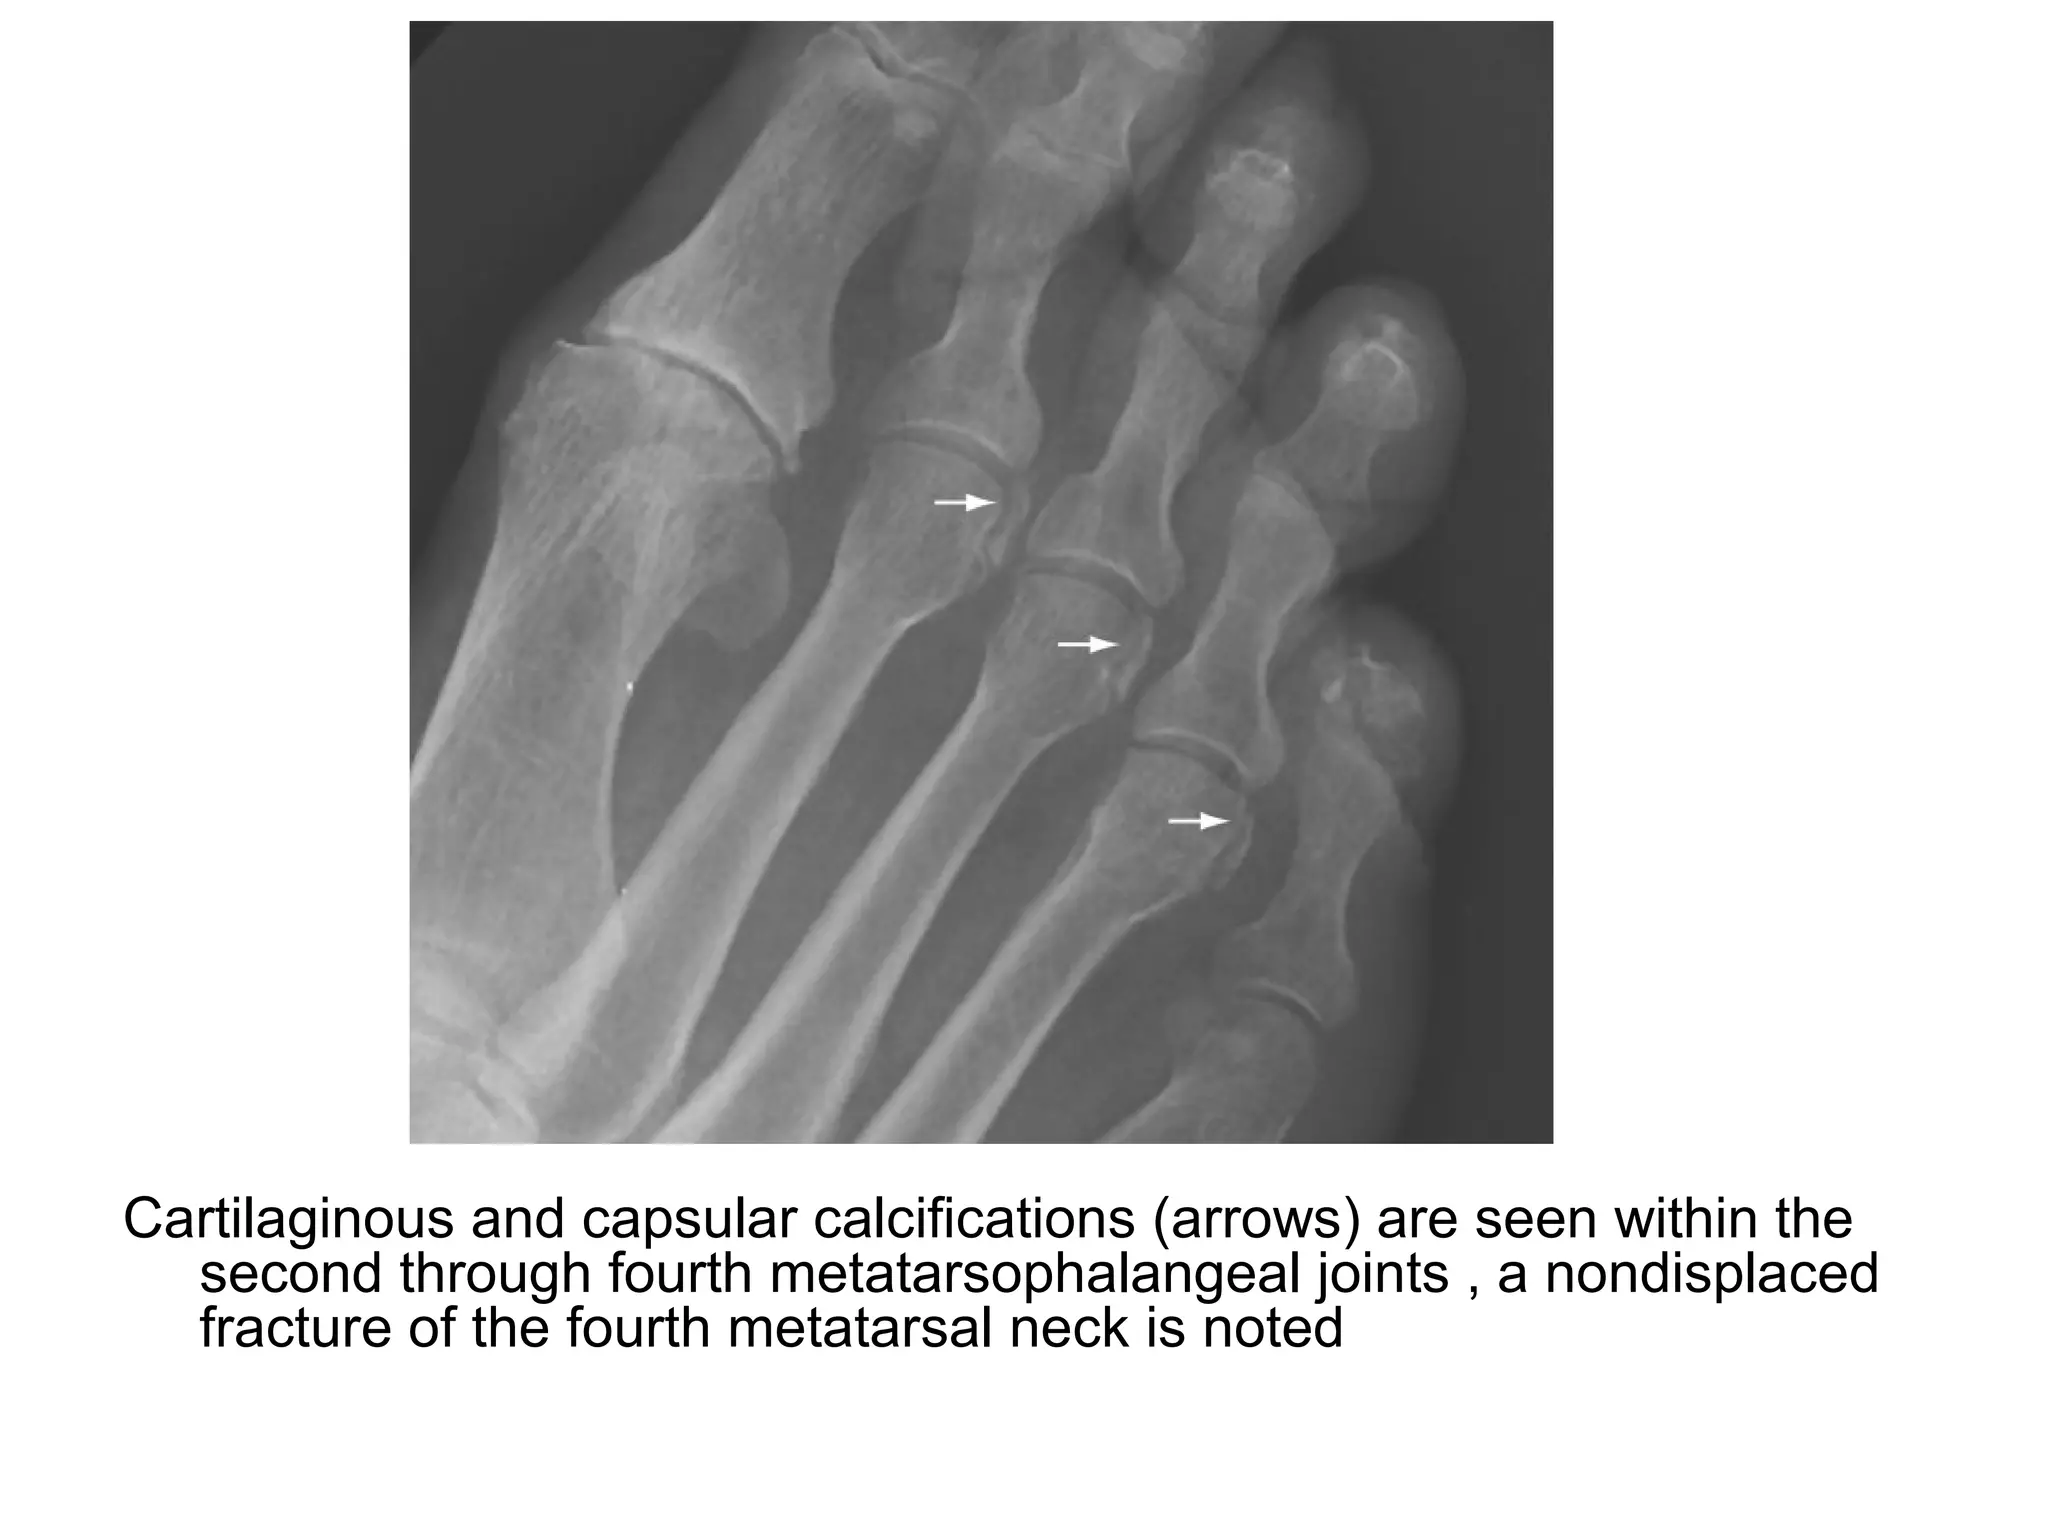

Cartilaginous and capsular calcifications (arrows) are seen within the

second through fourth metatarsophalangeal joints , a nondisplaced

fracture of the fourth metatarsal neck is noted